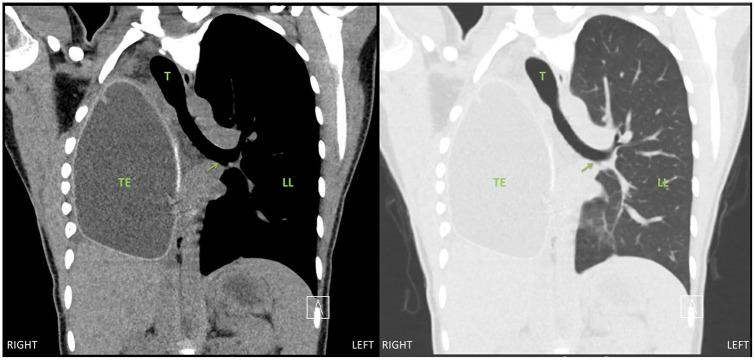

Postpneumonectomy syndrome is a rare complication in patients who have previously had a pneumonectomy. Over time, the mediastinum may rotate toward the vacant pleural space, which can cause extrinsic airway and esophageal compression. As such, these patients typically present with progressive dyspnea and dysphagia. There is a paucity of reports in the anesthesiology literature regarding the intraoperative anesthetic approach to such rare patients. We present a case of an 18-year-old female found to have postpneumonectomy syndrome requiring thoracotomy with insertion of tissue expanders. Our case report illustrates the complexities involved in the care of these patients with regards to airway management, ventilation concerns, and potential for hemodynamic compromise. This case report underscores the importance of extensive multidisciplinary planning.

肺切除术后综合征是既往行肺切除术患者的一种罕见并发症。随着时间的推移,纵隔可能向空的胸膜腔旋转,这可能导致气道和食管受压。因此,这些患者通常表现为进行性呼吸困难和吞咽困难。麻醉学文献中关于此类罕见患者的术中麻醉方法的报道很少。我们报告了一例 18 岁女性患者,发现患有肺切除术后综合征,需要行开胸手术并插入组织扩张器。我们的病例报告说明了在气道管理、通气问题以及潜在的血液动力学受损方面,对这些患者进行护理所涉及的复杂性。本病例报告强调了广泛的多学科规划的重要性。